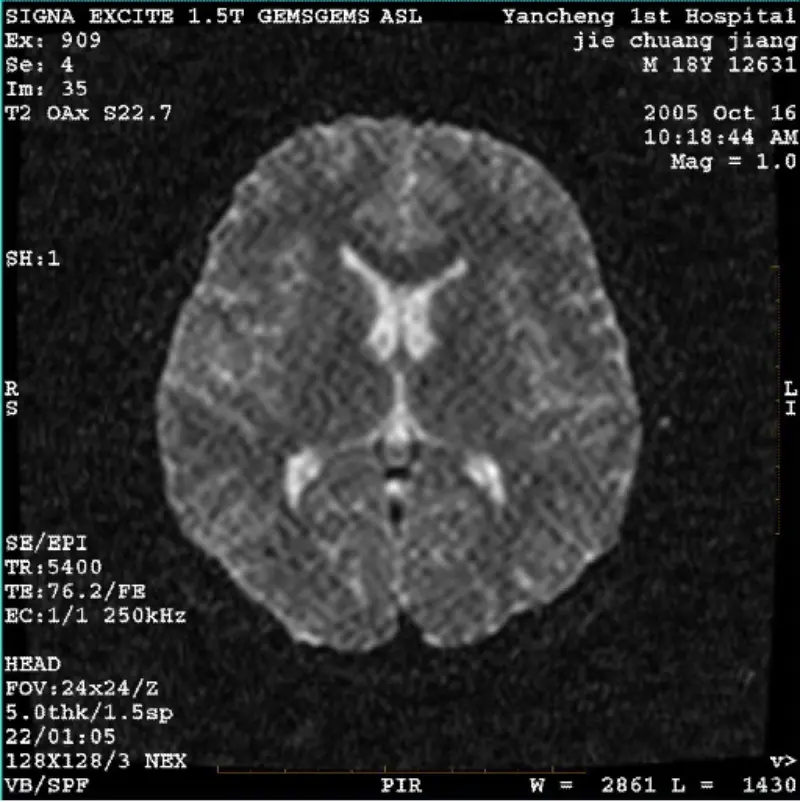

Läs merSYSTEM: 1.5T Signa Twin Excite II (programversion 11.0M4) PROBLEM/SYMPTO DWI (Zoomläge och helläge) och fiesta (zoomläge och helläge) bild med synlig nät- eller manchesterartefakt oavsett när du använder kroppsspole eller huvud spole, verkar annan rutinbild normal